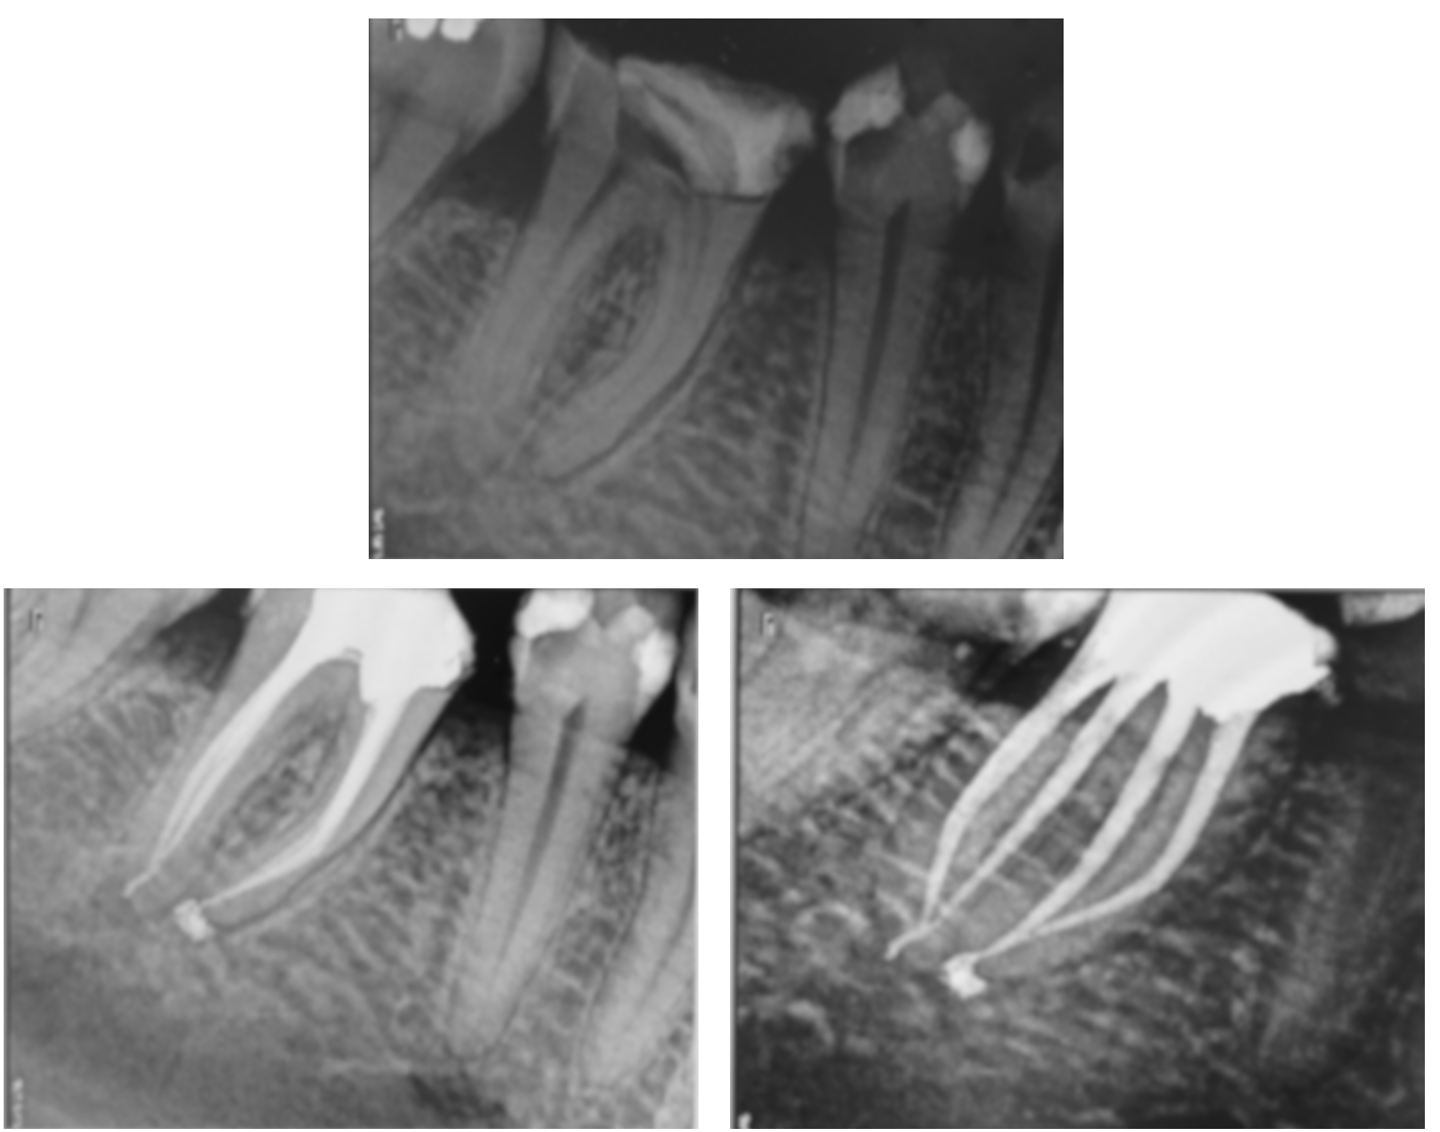

La réalisation du traitement : isolement, mise en forme, irrigation et obturation.

Le suivi : contrôler la réussite à long terme, tant cliniquement que radiographiquement.